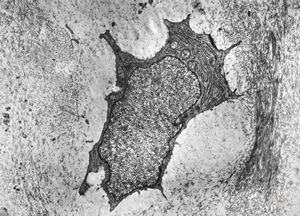

M,19y. | chondrocyte - chondrosarcoma - jaw